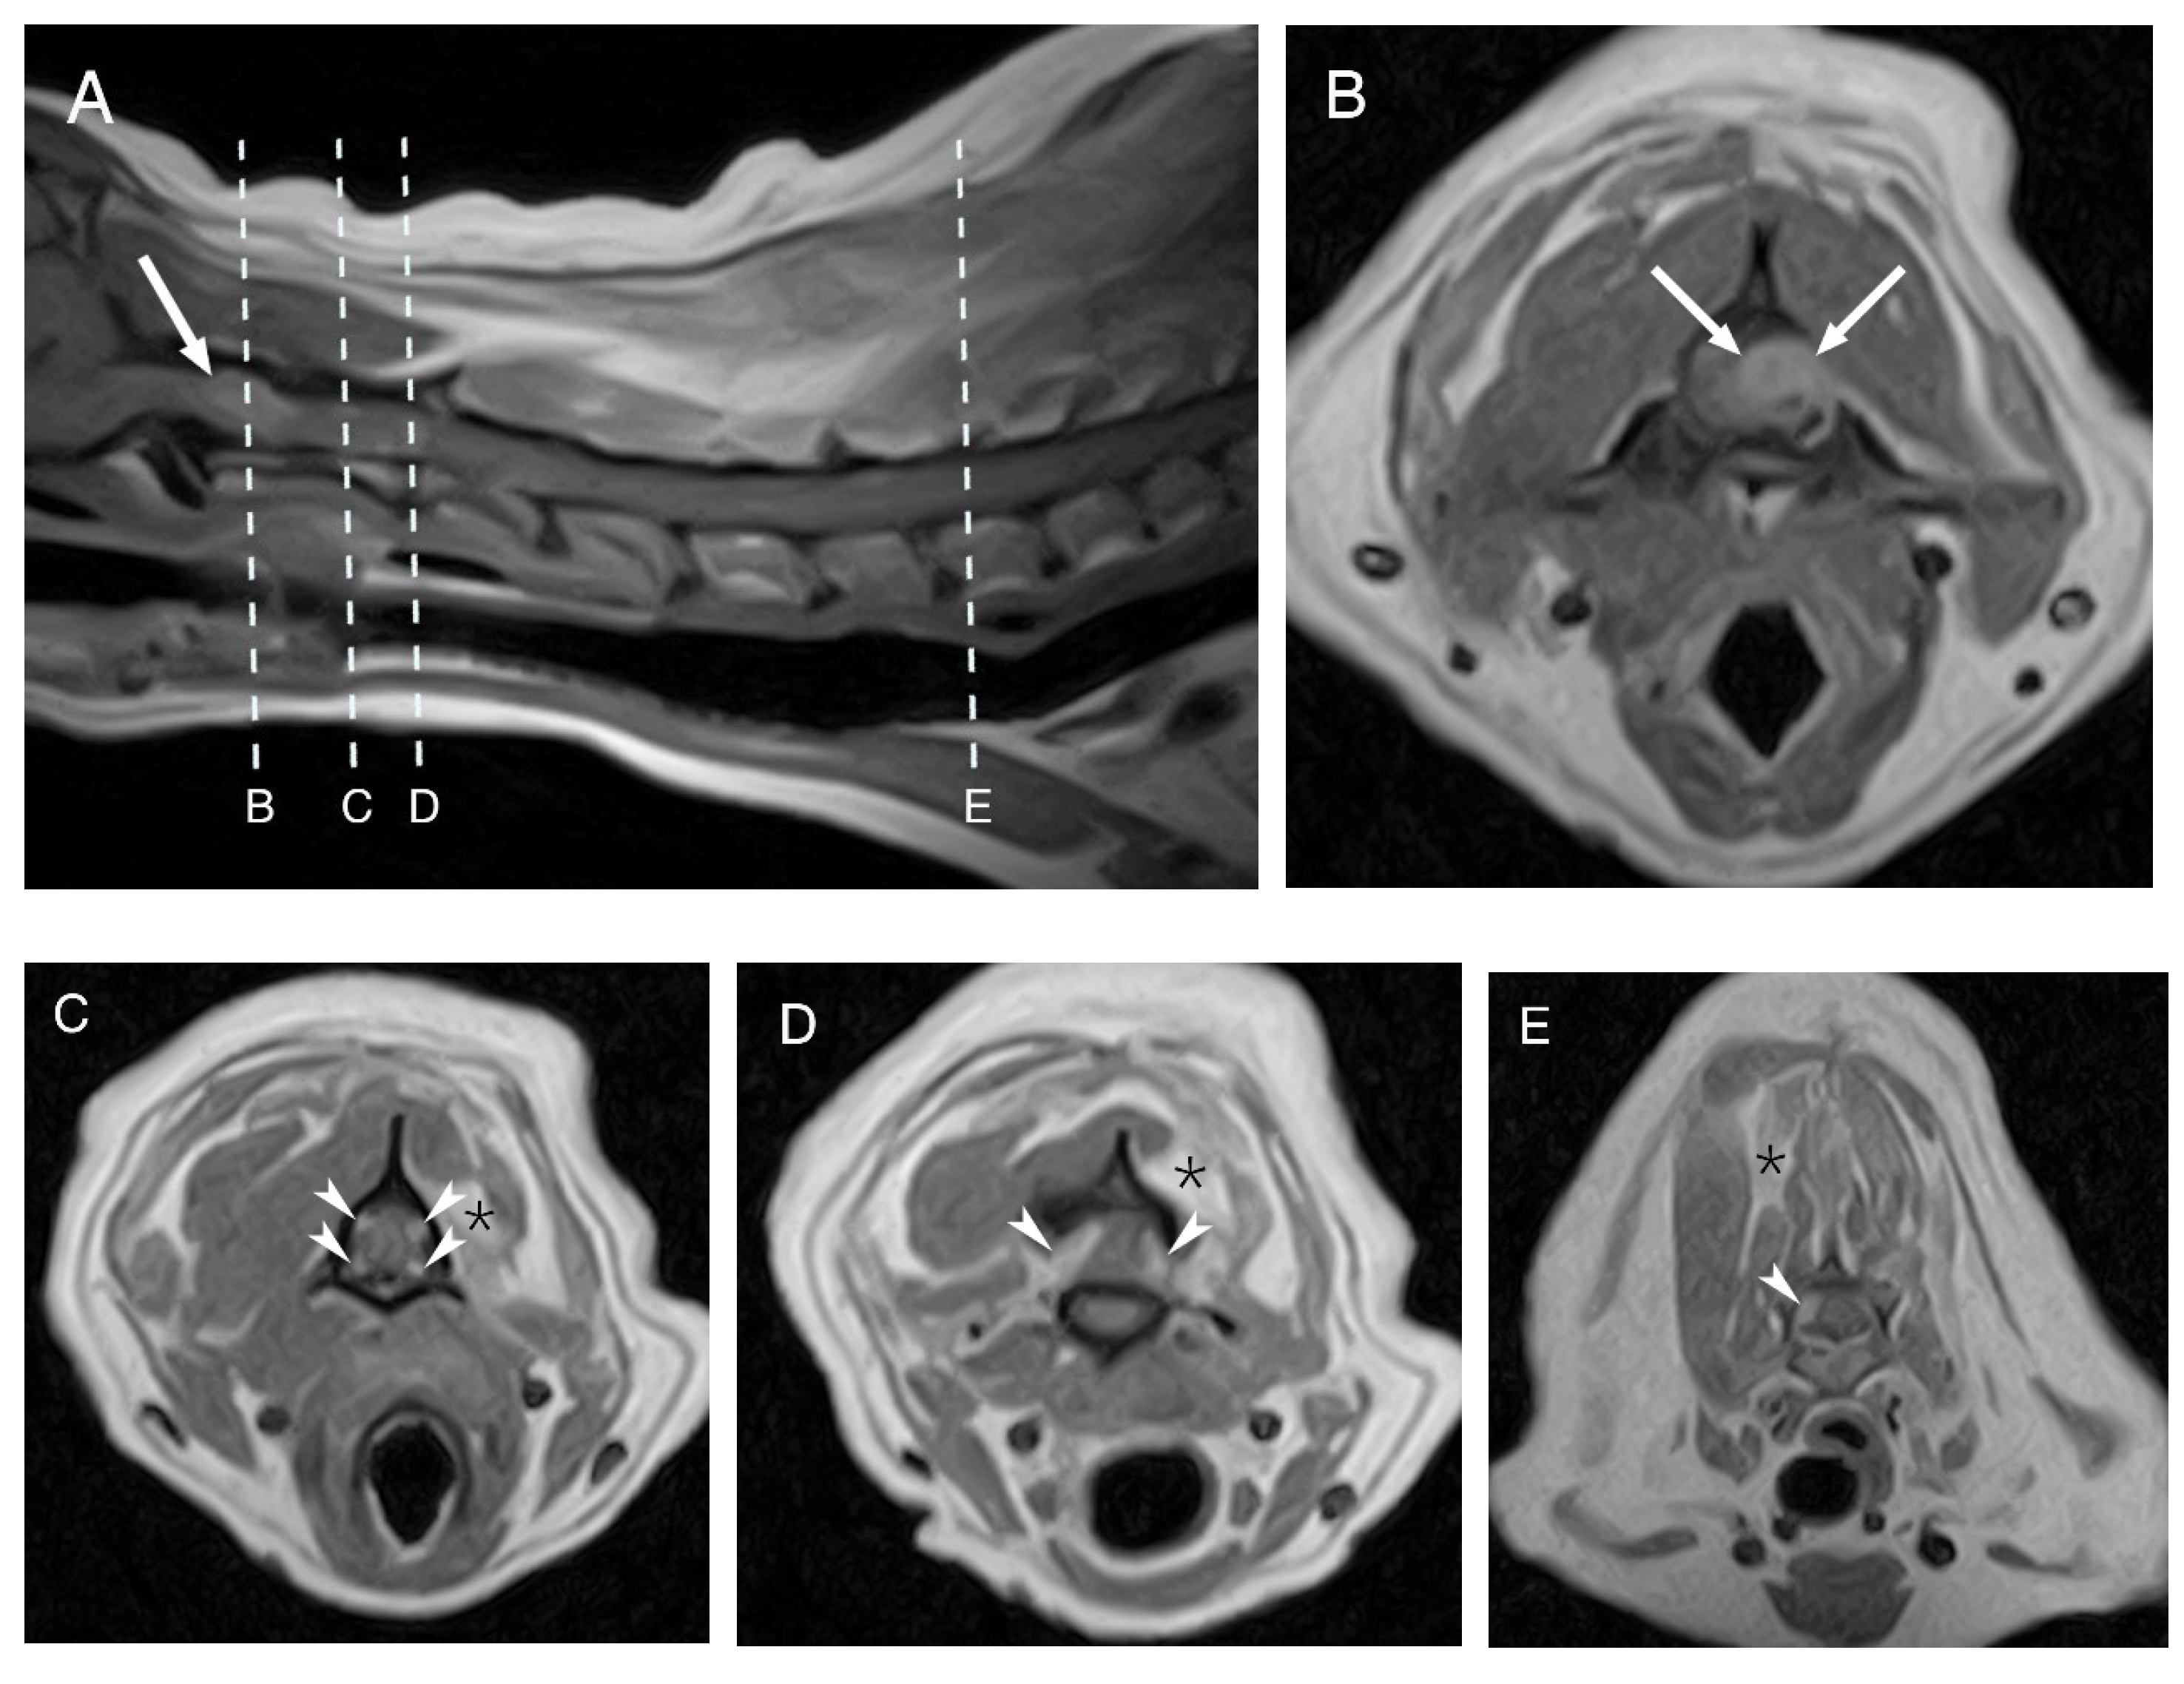

A follow-up MRI showed multiple, well-defined, intradural-extramedullary mass-like lesions affecting multiple spinal nerve roots along the cervicothoracic spinal cord. These lesions were T2W hyperintense and T1W isointense compared with the normal spinal cord parenchyma and showed a marked and homogeneous contrast enhancement. The largest mass (1.1 cm × 0.8 cm) was located at the level of the left C1–C2 intervertebral foramen and on the region of the left nerve root of C1, causing severe compression of the spinal cord. The remaining lesions had similar features but were only mildly compressing the spinal cord. The previously seen ill-defined intramedullary lesion T2W hyperintensity was less severe and extensive than on the first MRI, but was then more severe and visible at the level of C3, which was not visible on the first MRI scan. The adjacent hypaxial and epaxial muscles and the left supraspinatus and subscapularis muscles were moderately reduced in size with multifocal T2W hyperintense areas most consistent with denervation atrophy and secondary myosteatosis (Figure 2).

Figure 2.

Follow-up MRI of the dog’s cervical region. Midsagittal T1W post contrast image (A) and T1W post contrast transverse images at different levels (B–E). The arrows are pointing to the largest mass at the level of C1–C2 (A,B). The arrowheads are showing the multiple lesions affecting several ventral and dorsal nerve roots bilaterally at the level of C2 (C), C2–C3 (D) and C6 (E). The asterisks show the secondary muscles changes at the level of C2 (C), C2–C3 (D) and C6 (E).